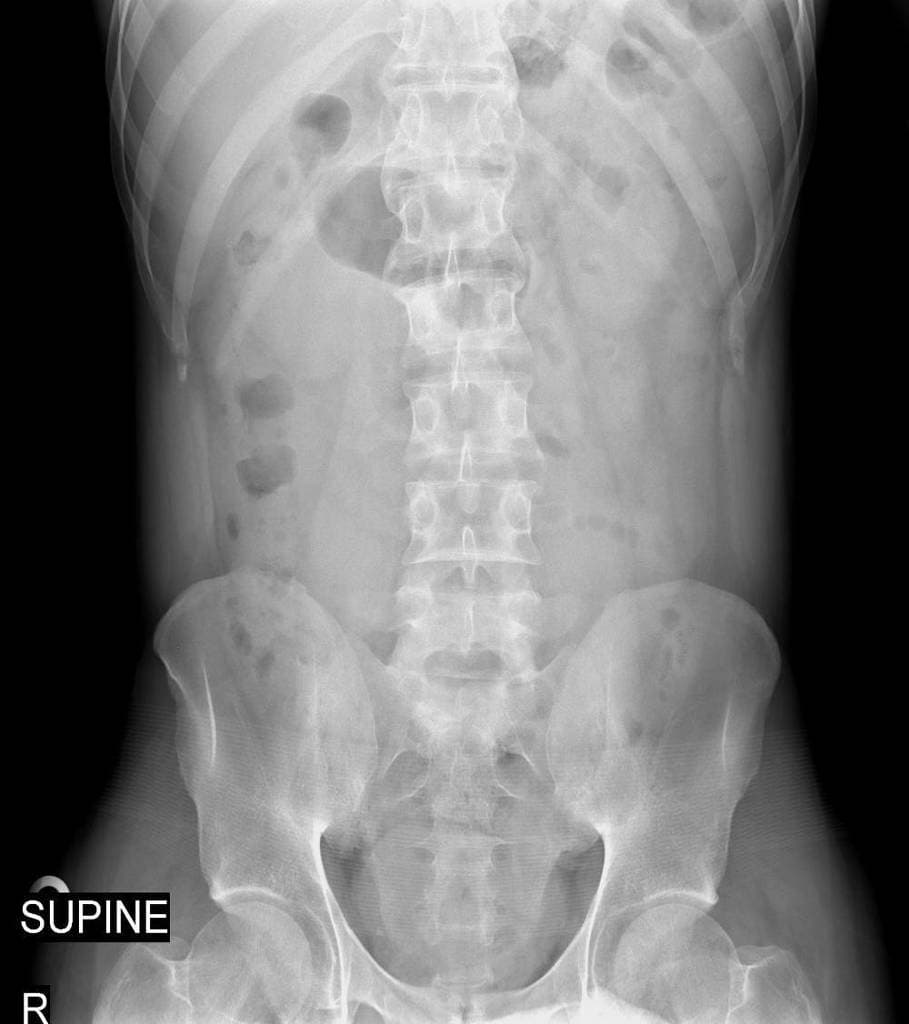

- Giải phẫu chuyển tiếp thắt lưng-xương cùng (có thể là hiện tượng bán hóa xương cùng của L5).

Bệnh nhân này có tiền sử dương tính với HLA B27 và viêm cột sống dính khớp, các phát hiện trên cộng hưởng từ (MRI) gợi ý viêm khớp cùng chậu hai bên (bilateral sacroilitis). Tuy nhiên, viêm khớp cùng chậu biểu hiện không đối xứng, rõ rệt hơn ở bên trái; do bên phải có giải phẫu chuyển tiếp thắt lưng-xương cùng, có thể tồn tại thêm tình trạng rối loạn cơ học khớp cùng chậu, góp phần vào hình ảnh bất đối xứng này.

- "Giải phẫu chuyển tiếp thắt lưng-xương cùng có thể gây căng thẳng cơ học lên khớp, làm trầm trọng thêm hoặc bắt chước tổn thương viêm."